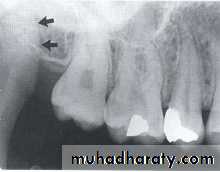

NUTRIENT CANALS

Nutrient canals carry a neurovascular bundle and appear as radiolucent lines of fairly uniform width. They are most often seen on mandibular periapical radiographs running vertically from the inferior dental canal directly to the apex of a tooth or into the inter dental space between the mandibular incisors.